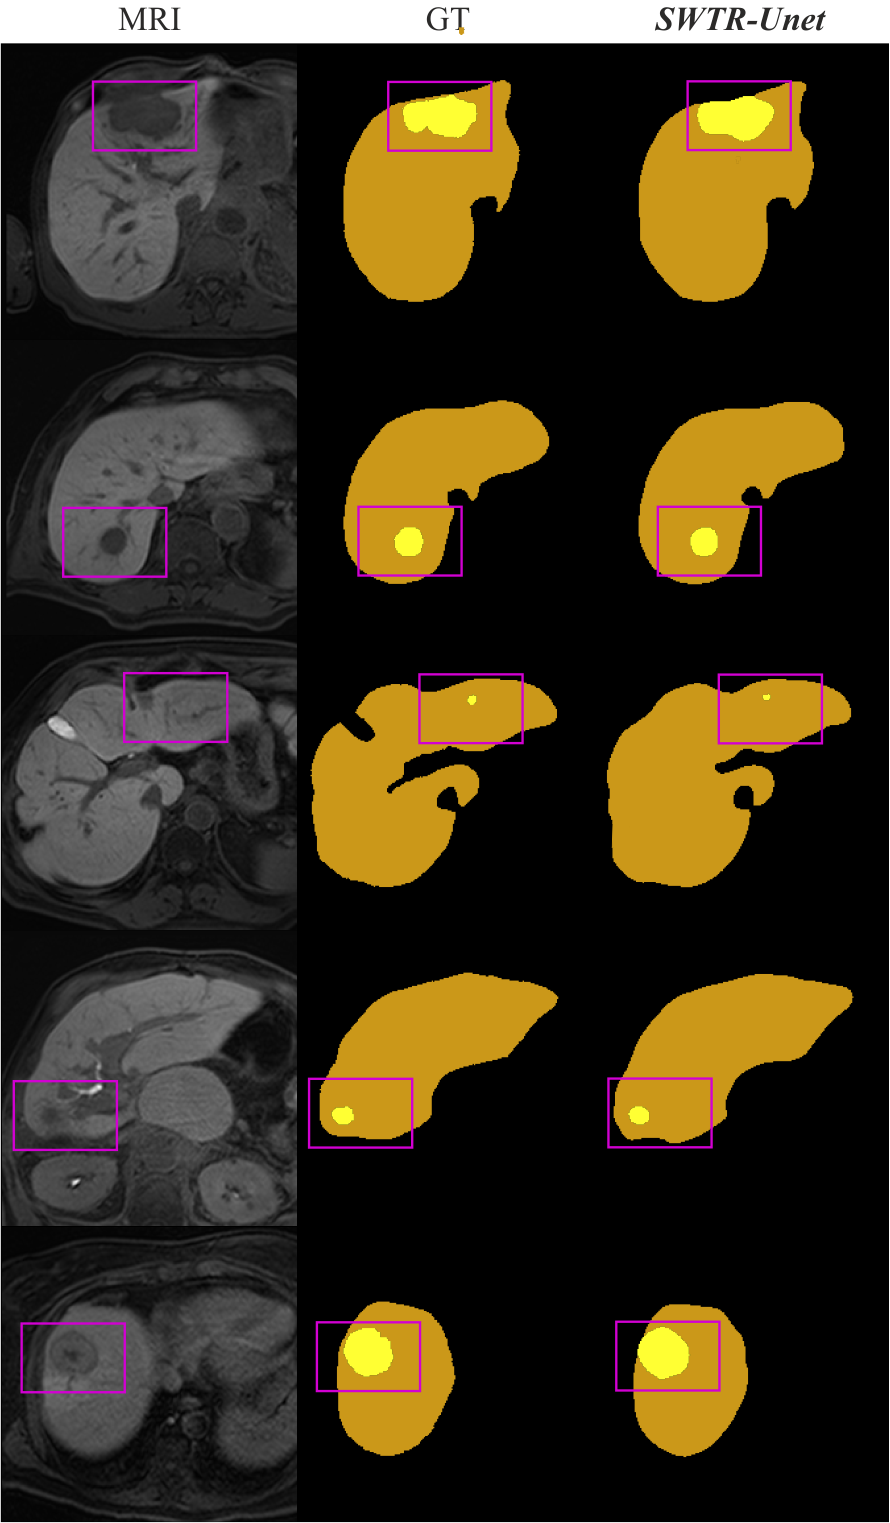

Table 2 shows the averaged segmentation accuracy of all implemented network variants, including both, multiple state-of-the-art architectures and the proposed SWTR-Unet regarding the liver outline and the hepatic lesions therein. With respect to the entirely convolutional-based network variants, the best results could be achieved with the nnUnet with on average liver and lesion Dice. Most of the other state-of-the-art CNNs show promising results regarding the liver segmentation, but lack accuracy in terms of the much more challenging segmentation of the hepatic lesions (see Figure 4). The observation of some of the networks producing the worst results revealed several possible reasons for the weak performance: a prevalent cause seems to be false-positive classified pixels in addition to otherwise reasonably good delineated tumors, which occurs on better performing samples as well but is less pronounced there. This problem is most prominent in the case of Unet and DeepLabV3 (average false-positive rate of and as compared to the of the DAF3D network). Furthermore, these networks are not able to sufficiently segment tumors of irregular shapes. Examples are shown in Figure 4, where the networks’ limitations of segmenting non-circular shaped lesions are demonstrated. Similar behaviour is observed for tumors of small size, which were not appropriately detected by any of the Unet, Attention Unet, and DeepLabV3 networks. Another challenge for those variants represented tumors located close to the liver boundary. In conclusion, the tested convolutional-based networks achieved acceptable segmentation accuracies regarding hepatic lesions of spherical shape, larger size and location in central regions of the liver, but the accuracies drastically decreased for non-spherical shaped and small tumors that are located close to the liver surface. In contrast, transformer-based networks achieved overall higher segmentation accuracies especially regarding the hepatic lesions. The only exception to this was the UnetR variant, which lacked sufficient accuracy for both object classes. The proposed SWTR-Unet variant outperformed any other network in this test in terms of liver and hepatic lesion segmentation, resulting in DSCs on average of and , respectively. Furthermore, in comparison to most of the state-of-the-art network variants, the proposed SWTR-Unet seemed to widely overcome limitations due to smaller sized and non-spherical shaped lesions.